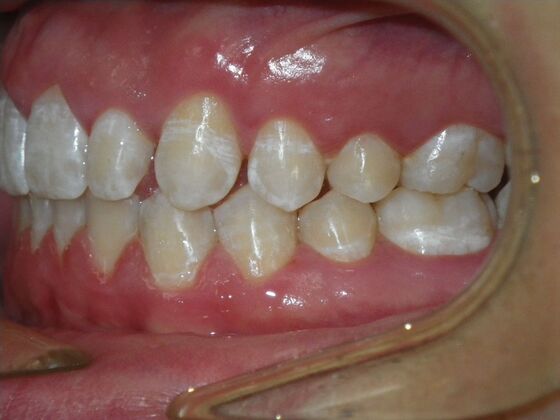

This patient does not like his anterior deep bite and the flaring of the right lateral incisor as well as anterior spacing. The solution was to correct his Class II molar relationship, Division II and deep anterior bite and close spacing as much as possible with addition of composite restorations on distals of lateral incisors. We began with utility archwires, eventually correcting Class II molar with distalizing appliance, and continued with final tip and torque. All that is left now is to ad composite to distals of upper lateral incisors.